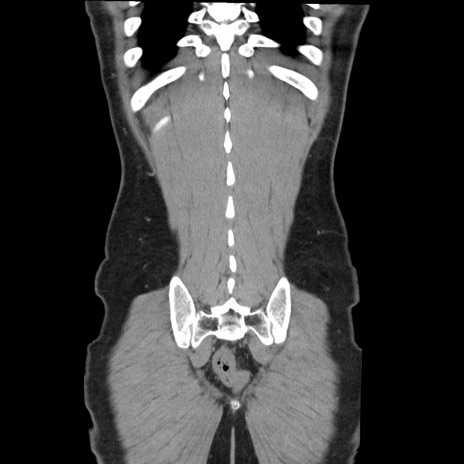

症例36(冠状断像)

【症例】20歳代 男性

【主訴】心窩部痛

【現病歴】今朝より上腹部痛あり。一旦軽快していたが再度出現したため救急要請。昨日夕に白身の魚を含む刺身を食べた。

【身体所見】BP 136/89mmHg、HR 74/min、BT 37.0℃、腹部:膨満、軟、心窩部に圧痛あり。反跳痛なし、筋性防御なし、腸雑音やや亢進あり。

【データ】WBC 17700、CRP 0.48